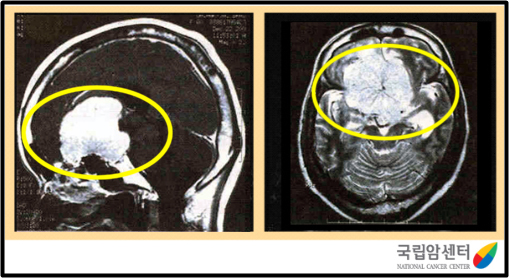

[ 전두엽에 발생한 수막종의 뇌 자기공명영상 사진 ]

자기공명영상(MRI)나 전산화단층촬영(CT) 영상으로 종양의 위치나 크기는 물론 양성인지 악성인지 여부도 알 수 있습니다. 그러나 가장 정확한 방법은 수술 중에 나온 종양 조직을 현미경으로 검사하는 것입니다. 조직 검사는 수술장에서 즉시 하는 동결조직 검사와 수술 후 결과가 나오기까지 약 1주일 정도 걸리는 최종 조직 검사가 있습니다. 최종 조직 검사는 각종 특수 염색을 하며 가장 정확한 진단 방법입니다.